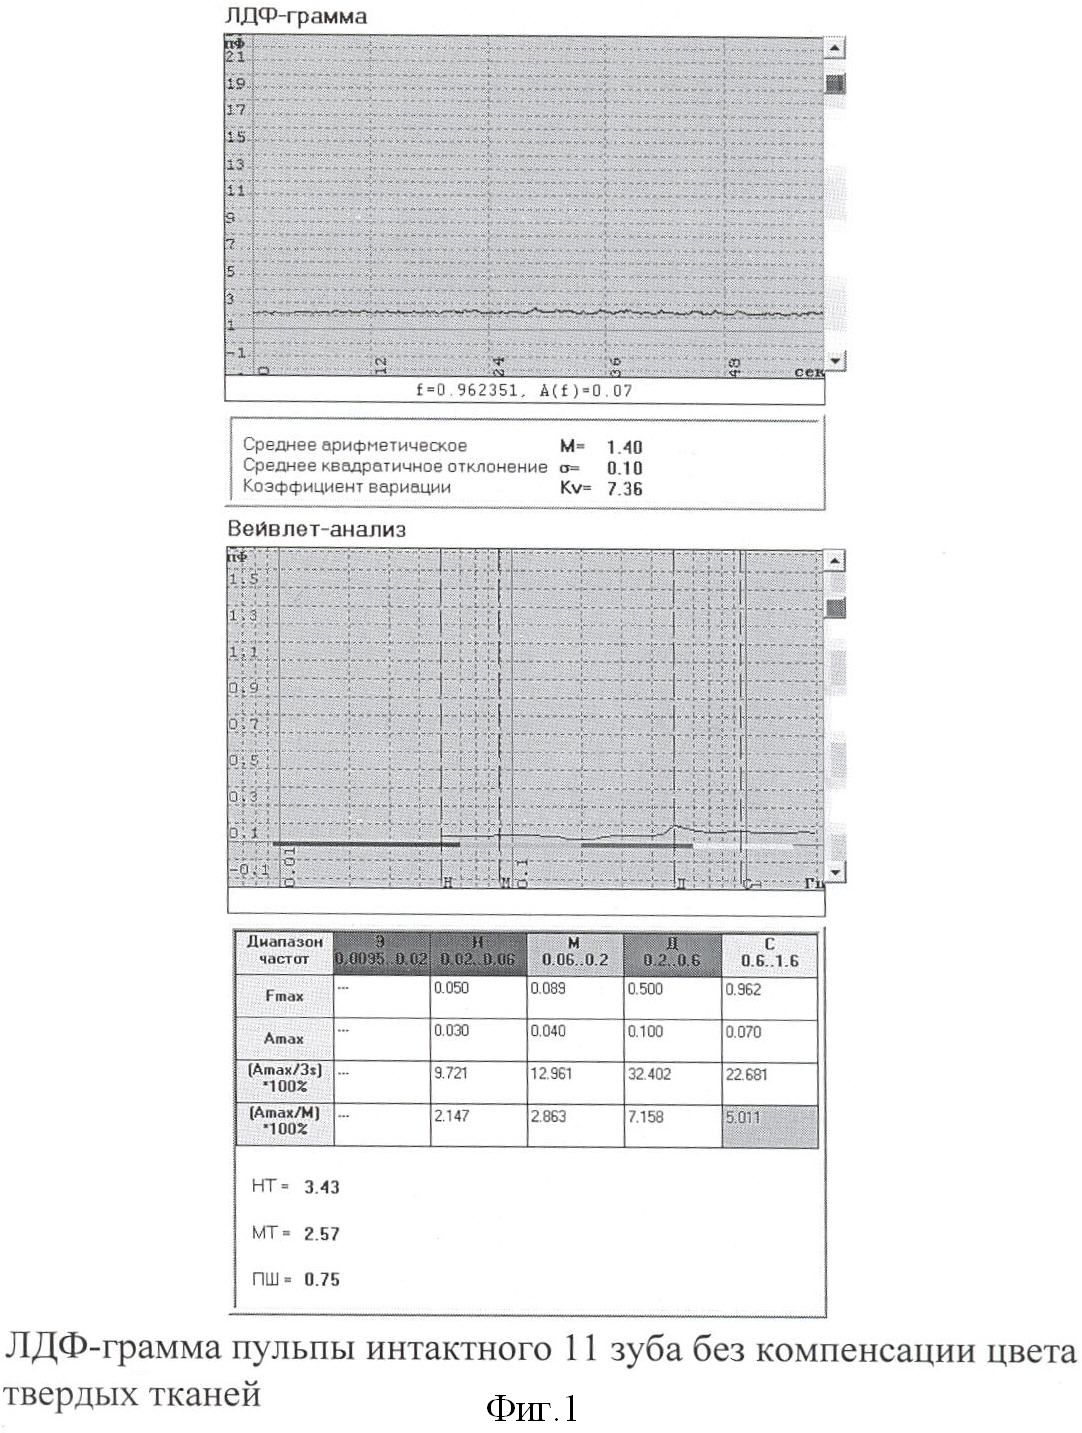

При регистрации ЛДФ-граммы традиционным способом ПМ составил 1,4 ПЕ (фиг.1.), а с помощью цветовой компенсации твердых тканей зуба – 9,43 ПЕ (фиг.2.). При анализе амлитудно-частотного спектра с помощью Вейвлет-преобразования видно, что сердечный ритм при цветовой компенсации зуба превышает таковой без аппаратной компенсации в 20,7 раза, дыхательный – в 4,9 раза и миогенный – в 17 раз (фиг.1, 2.).

Для сравнительной оценки полученных данных в эксперименте проводили регистрацию ЛДФ в пришеечной области на 2 мм выше десневого края в зоне предполагаемого выступа пульпы депульпированного 36 зуба с предварительным выставлением биологического нуля традиционным способом (белая фторопластовая пластина) (фиг.3.). На ЛДФ-грамме видно, что уровень сигнала соответствует 1,16 ПЕ. На фиг.4 после воздействия на твердые ткани зуба когерентным лазерным излучением и обработки сигнала методом компенсации цвета зуба с верхней трети коронки на допплерограмме значения показателя микроциркуляции (ПМ) составили 0,01 ПЕ, что и соответствует биологическому нулю.